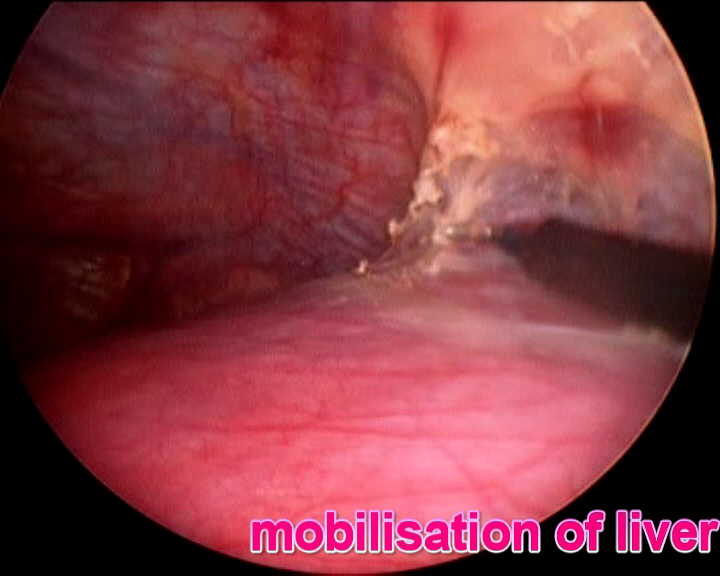

Laparoscopic Liver, Pancreas and Bilary Surgery

are advanced surgical procedures that requires adequate training in traditional open surgery as well as proficiency in laparoscopic techniques. Relevant and adequate training in step-wise manner up the ladder of complexity should be acquired by surgeons offering this approach coupled with adoption of modern instrumentation and equipment to ensure safe execution of the surgical procedures.

- Liver resection (for cancer and other liver tumor)